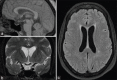

Figures